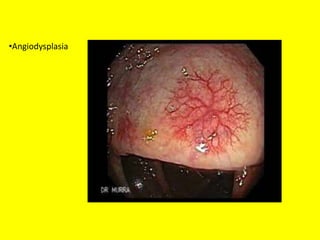

• Angiodysplasia of the colon

•Angiodysplasia